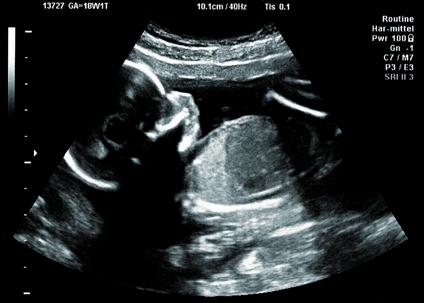

fetus